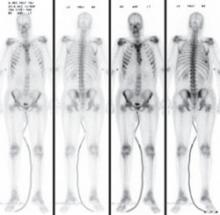

Cytological examination of the pleural fluid revealed adenocarcinoma of the lung. A diagnosis of adenocarcinoma of pulmonary origin was supported by immunohistochemical tests that were positive for thyroid transcription factor 1, cytokeratin 7, carcinoembryonic antigen, and epidermal growth factor receptor (EGFR), which made findings from other sites of adenocarcinoma less likely. A bone scan revealed metastases to the sixth rib and sternum, indicating stage IV adenocarcinoma (FIGURE 3).

FIGURE 3

Bone scan reveals metastases